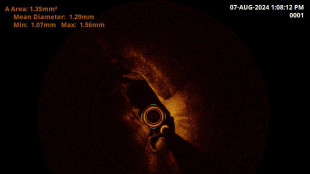

Per un sorriso perfetto scoperti non più di tre millimetri

SIdP, progettare l'impianto dentale con la Tac 3D e con innesti